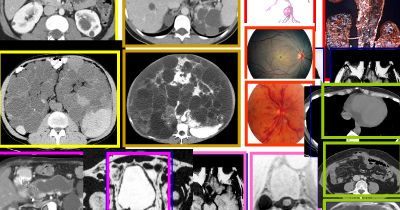

Moderately advanced autosomal dominant polycystic kidney disease.

End-stage autosomal dominant polycystic kidney disease.

Coronal MR and CT images of a patient with typical ADPKD and another with markedly asymmetric liver involvement.

Wide spectrum of disease severity and extrarenal manifestations (intracranial aneurysms, thoracic aortic dissection, retinal artery and vein occlusions, pericardial effusion, pancreatic cysts and intrapapillary mucinous neoplasm, seminal vesicle cysts, arachnoid cyst, dural diverticulum, colonic and duodenal diverticula).

Stability of two small intracranial aneurysms detected by presymptomatic screening.

Typical infantile appearance of autosomal recessive polycystic kidney disease.